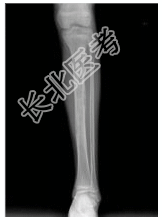

- [材料题] 患者女,10岁,左胫骨不适。查体:左胫骨压痛,皮肤无明显红肿,无明显软组织肿块。行左胫腓骨正侧位片检查。

- 简答题1、患者的诊断及依据是什么?

- 简答题2、鉴别诊断是什么?